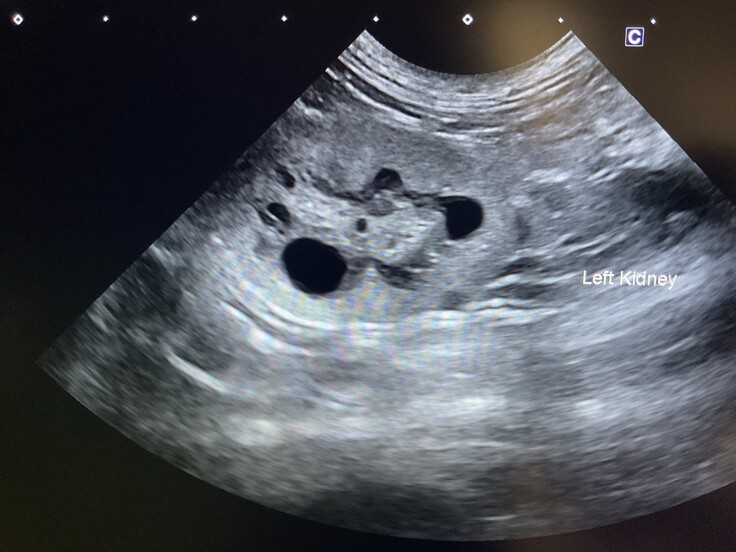

※病院での検査結果

・推定年齢:10歳

・骨盤骨折

・両腎嚢胞

・貧血、低アルブミン、白血球数上昇

・重度のノミ感染

・歯周病、歯石

・エイズ白血病:陰性

夜間にミケコちゃんを見ていたため分かりませんでしたが、左耳に小さな耳カットがあり、避妊手術済であることが判明しました。また、愛護センターに確認したところ、該当する迷子届けは出ていませんでした。

診断結果から、今後も腎臓や口腔の治療が必要になる見込みです。